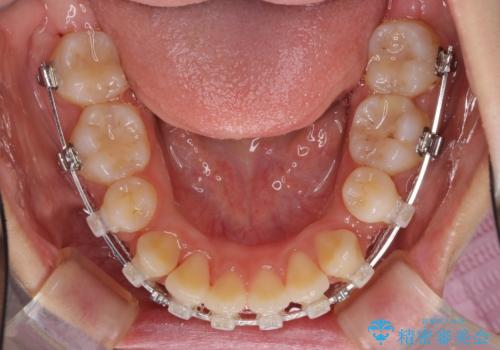

- 矯正装置

- ハーフリンガル

- 口元の突出感を気にして来院された患者様です。

上下左右の第一小臼歯4本を抜歯して口元を下げる治療計画としました。

目立たない装置が希望であったため、上顎が裏側装置である、ハーフリンガル装置を選択されました。

3年半ほどで終わる予定でしたが、途中引っ越し、出産、引っ越し、出産を繰り返し、なかなか来院することができず、装置を外すまでに8年以上の期間がかかってしまいました。